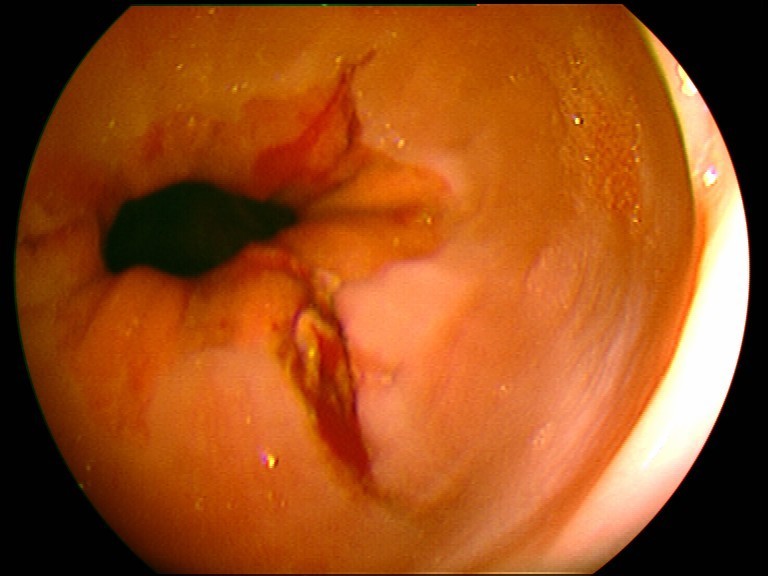

Gastroskopie - Mallory-Weiss-Syndrom (Schleimhautriss am Mageneingang nach heftigem Erbrechen)